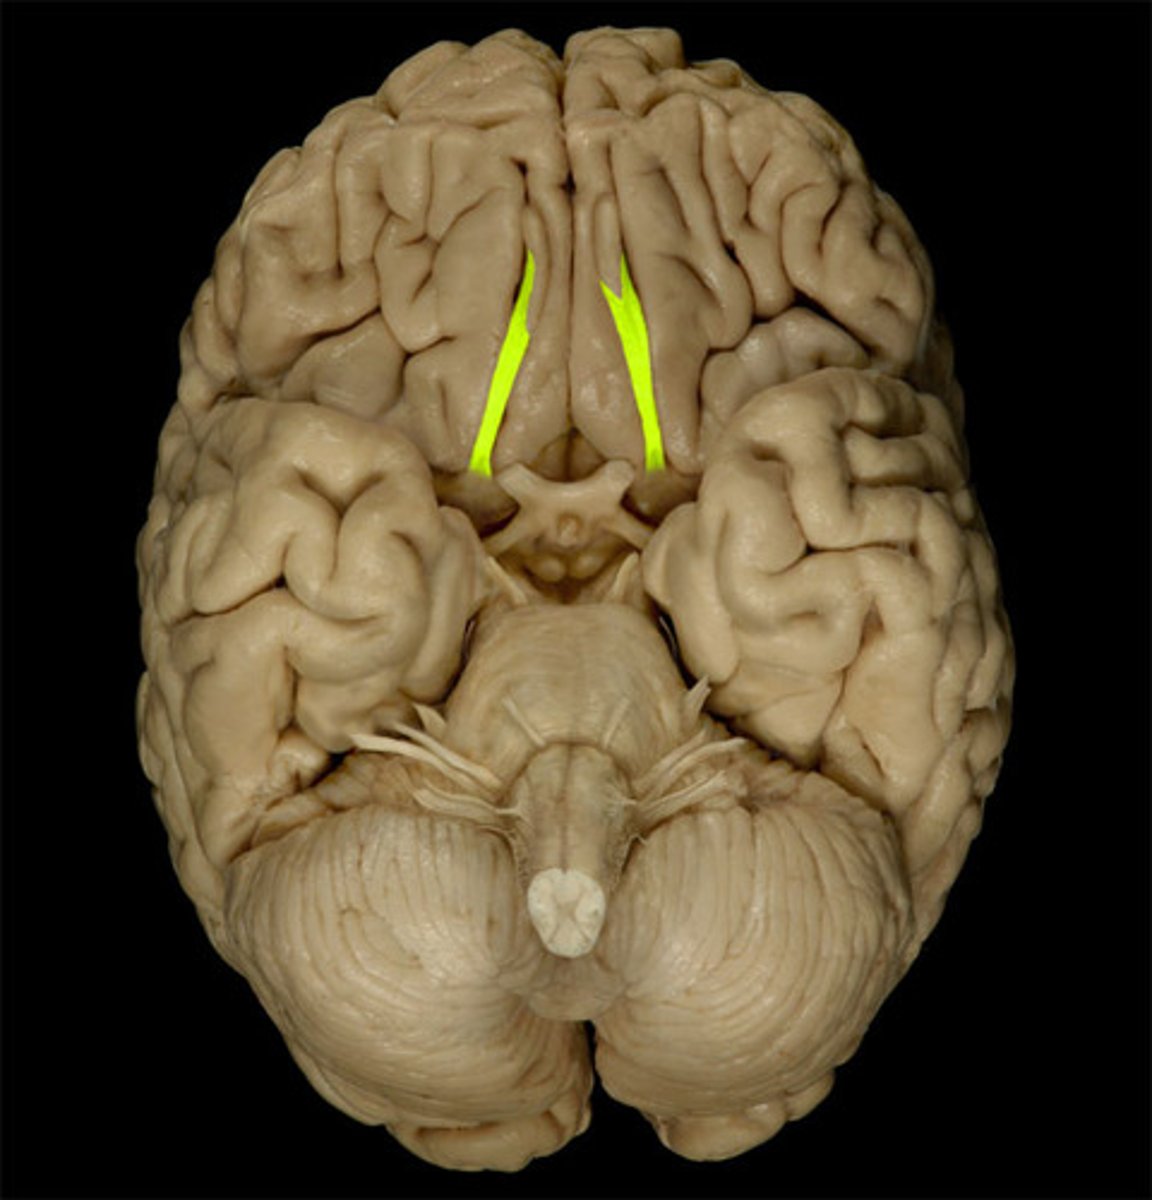

Olfactory Bulb

Optic Chiasm

Mammillary Bodies

Pons

Medulla Oblongata